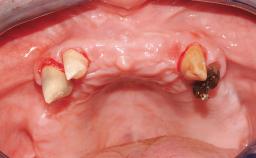

A 63-year-old male patient was referred for a consultation and treatment of partial edentulism in the maxilla. The patient presented with residual anterior teeth and declined a partial removable prosthesis. He reported that the maxillary posterior teeth had been extracted due to mobility and periodontal disease two months before the consultation. The patient’s chief complaint was that his residual maxillary teeth were mobile and that he was unable to chew. The patient’s desire was a stable and comfortable fixed maxillary rehabilitation. The patient was a light smoker (fewer than 10 cigarettes/ day), and his medical history was without significant findings. He was not on any regular medication at the time of consultation. The extraoral examination revealed a normal physiognomy with a correct distribution of the facial thirds. The patient presented a low lip line, and the transition line between teeth and soft tissues was not exposed during a forced smile.

Defining Characteristics Fully edentulous upper jaw to be rehabilitated with four or more implants